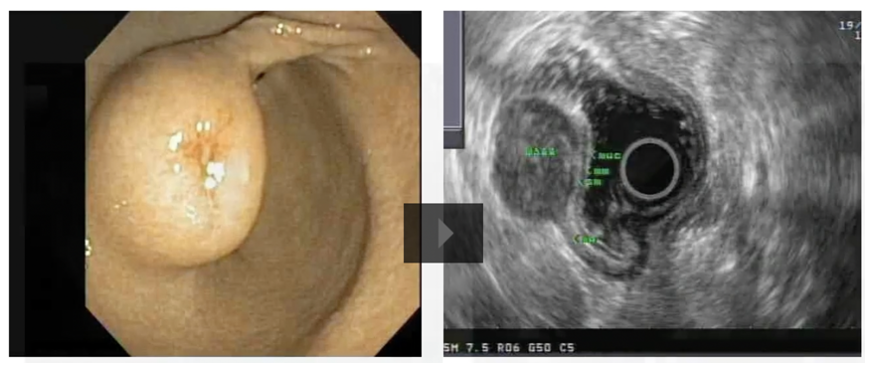

24

gastric duplication cyst